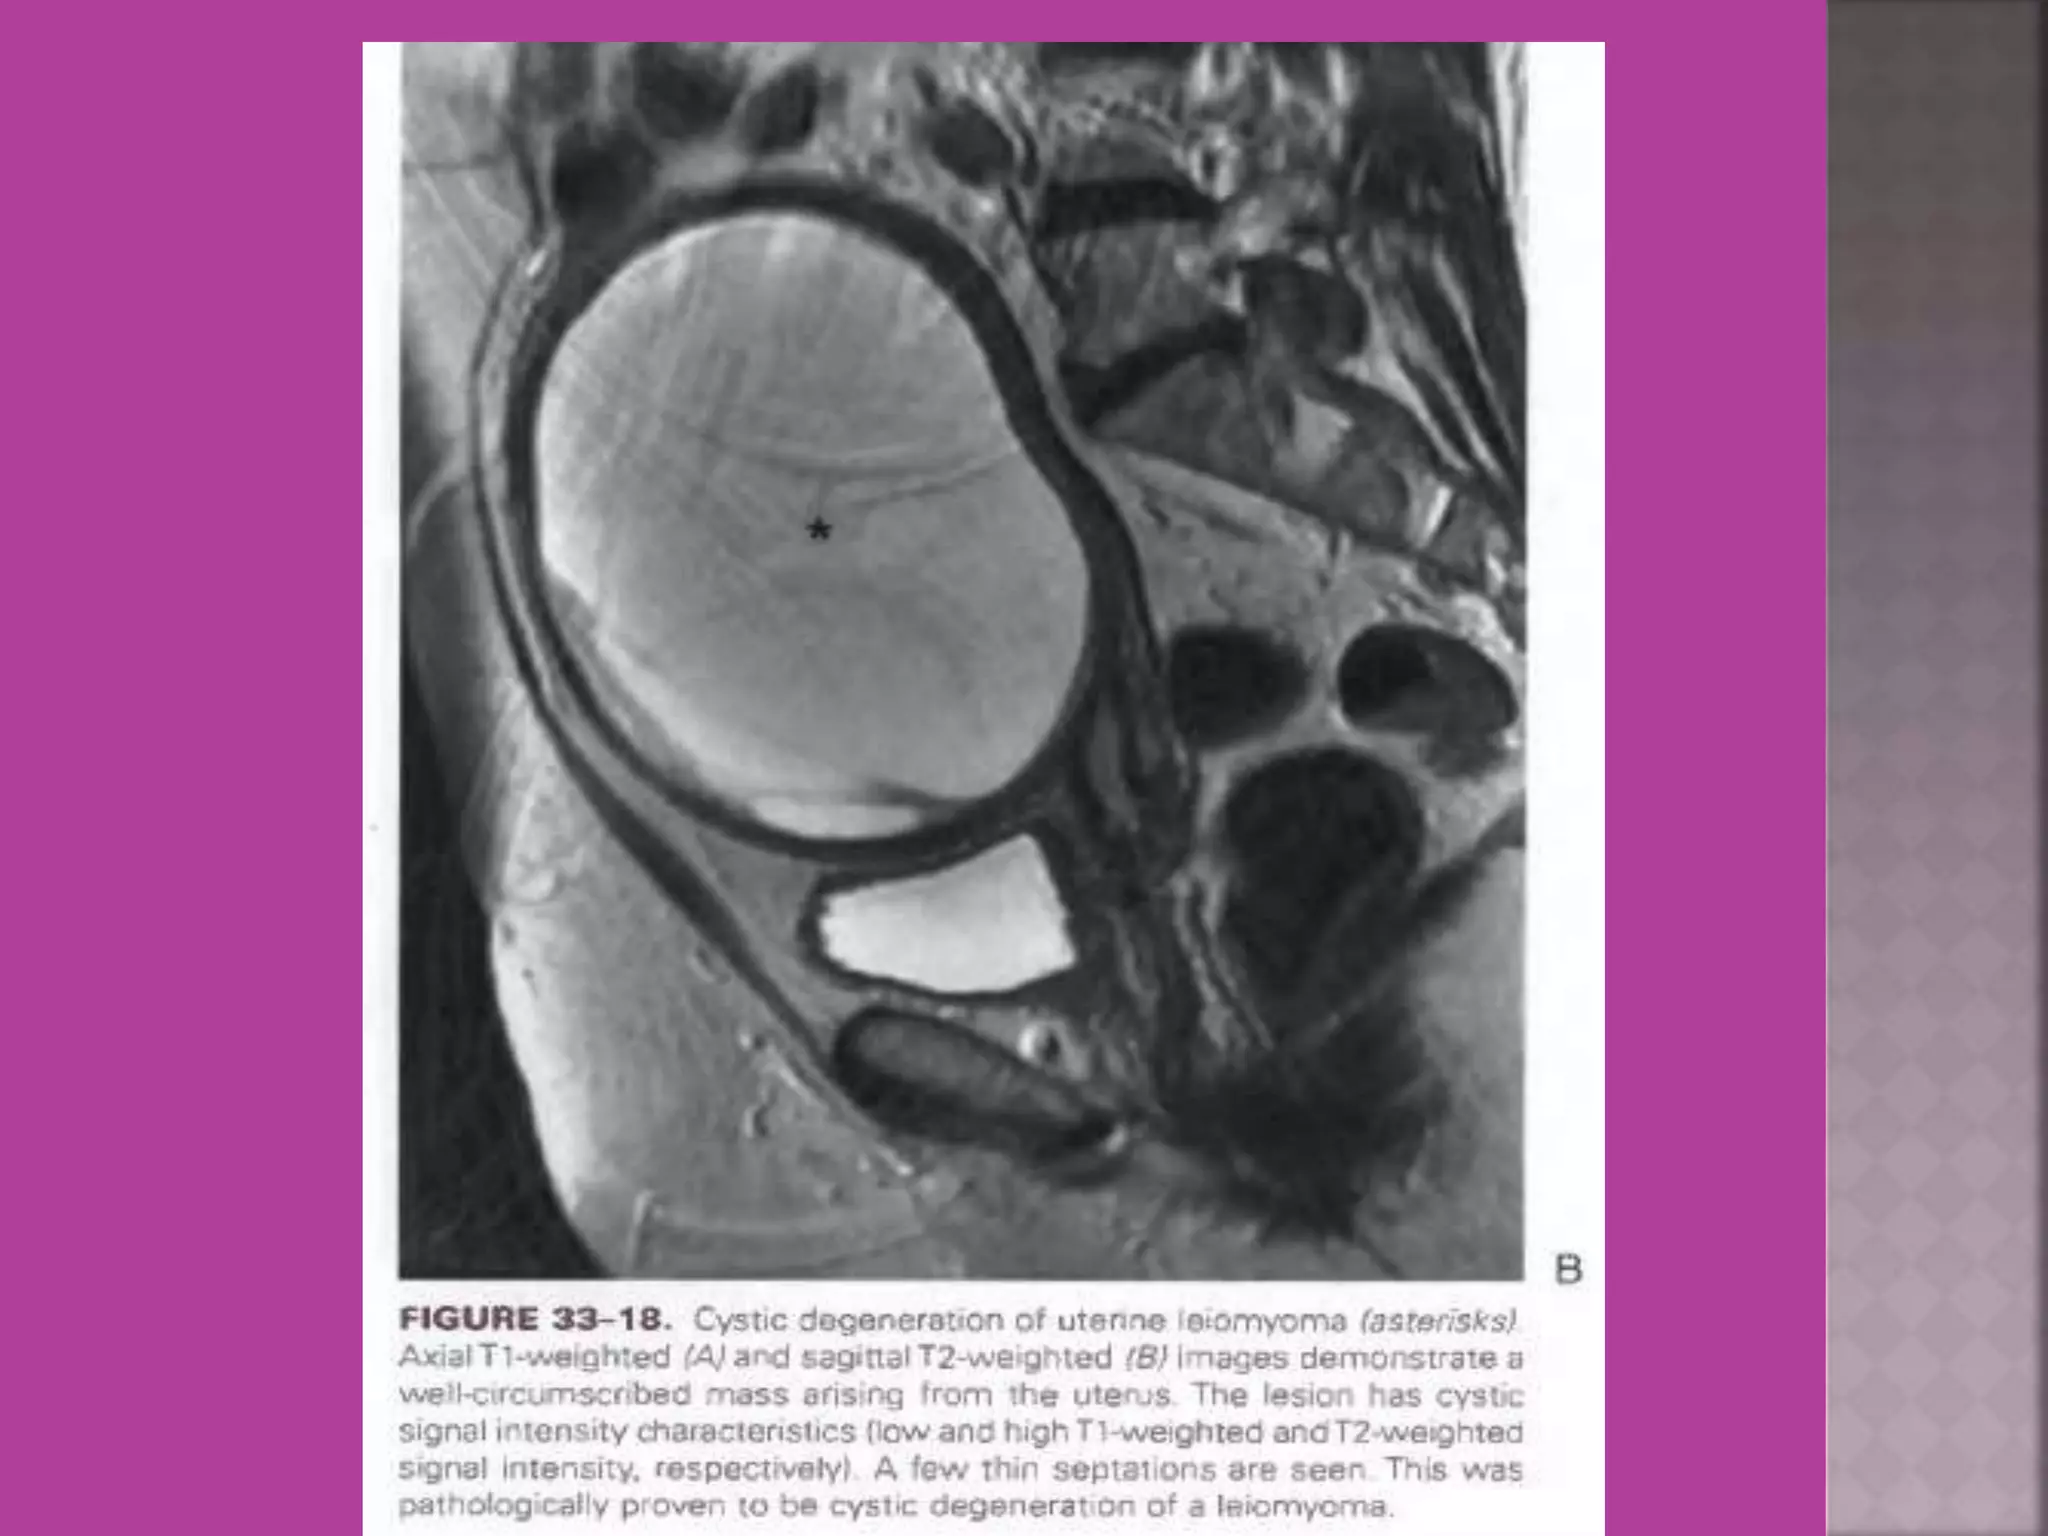

Degeneration Of Fibroid

Cystic Degeneration of

Fibroid